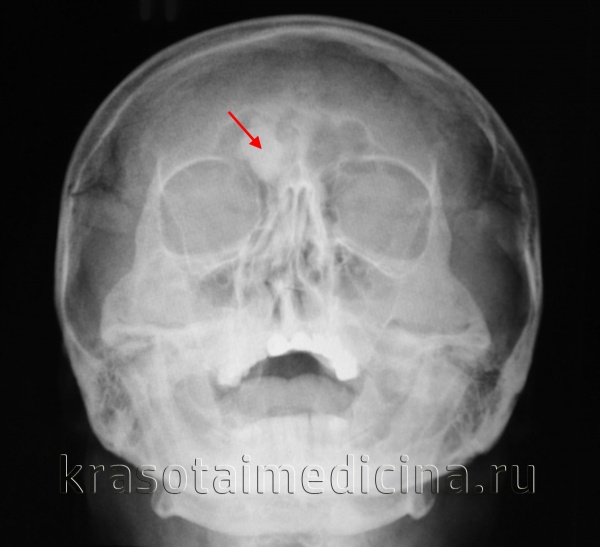

Рентгенограмма остеоид-остеомы проксимального отдела бедра. Имеется рентген-прозрачное образование с четкими контурами, окруженное склерозированной костью. Размеры прозрачного участка всегда меньше 1,5 см. Рентгенограмма голени в прямой проекции: остеоид-остеома малоберцовой кости. Обратите внимание на доброкачественный характер реакции кортикального слоя и увеличение объема кости. Остеоид-остеома диафиза бедра. Обратите внимание на утолщение кортикального слоя кости и доброкачественное периостальное новообразование костной ткани. Еще одним характерным признаком заболевания является интрамедуллярный склероз (стрелка). После рентгенографии методом выбора для диагностики остеоид-остеом является КТ, — очень чувствительный метод обнаружения при интра- и юкстакортикальном расположении «гнезда». Такое поражение сопровождается значительным утолщением кортикального слоя. Обратите внимание на случайное близкое расположение питающей артерии. Очень чувствительным методом диагностики остеоид-остеом является сцинтиграфия костей. В данном случае отмечается значительное усиление сигнала от пораженных дистальных отделов бедренных костей. Аксиальный КТ-срез (а) и взвешенный по Т2 МР-скан (б) с типичными признаками юкстакортикальной остеоид-остеомы дистального отдела бедра. На КТ виден типичный медуллярный склероз вокруг образования. На МРТ—выраженный сопутствующий отек костного мозга и периостальная реакция прилежащей надкостницы. Отечность проксимальной фаланги указательного пальца вследствие остеоид-остеомы. Интраоперационная картина «гнезда». Макропрепарат. «Гнездо» обычно имеет вишневокрасную окраску. При микроскопическом исследовании видны тонкие, хаотично расположенные остеоидные трабекулы, между трабекулами располагается богатая сосудами рыхлая соединительная ткань. При большем увеличении в веществе остеоида видны одинакового вида остеобласты без атипии ядер.

В ходе рентгенологического исследования под кортикальной пластинкой выявляется небольшой округлый участок просветления, окруженный зоной остеосклероза, ширина которой увеличивается по мере прогрессирования заболевания. На начальном этапе определяется четко видимая граница между ободком и центральной зоной остеомы. В последующем эта граница стирается, так как опухоль подвергается обызвествлению.

Представляет собой неподвижное, гладкое, плотное безболезненное образование. На рентгенограмме костей черепа компактная остеома отображается в виде овального или округлого плотного гомогенного образования с широким основанием, четкими границами и ровными контурами. На рентгенограммах трубчатых костей губчатые и смешанные остеомы выявляются, как образования, имеющие гомогенную структуру и четкие контуры. Лечение – удаление остеомы в сочетании с резекцией прилегающей пластинки. При бессимптомном течении возможно динамическое наблюдение.

Опухоль кости, состоящая из остеоида, а также незрелой костной ткани. Характерны малые размеры, хорошо заметная зона реактивного костеобразования и четкие границы. Чаще выявляется у молодых мужчин и локализуется в трубчатых костях нижних конечностей, реже – в области плечевых костей, таза, костей запястья и фаланг пальцев. Как правило, проявляется резкими болями, в отдельных случаях возможно бессимптомное течение. На рентгенограммах выявляется в виде овального или округлого дефекта с четкими контурами, окруженного зоной склерозированной ткани. Лечение – резекция вместе с очагом склероза. Прогноз благоприятный.